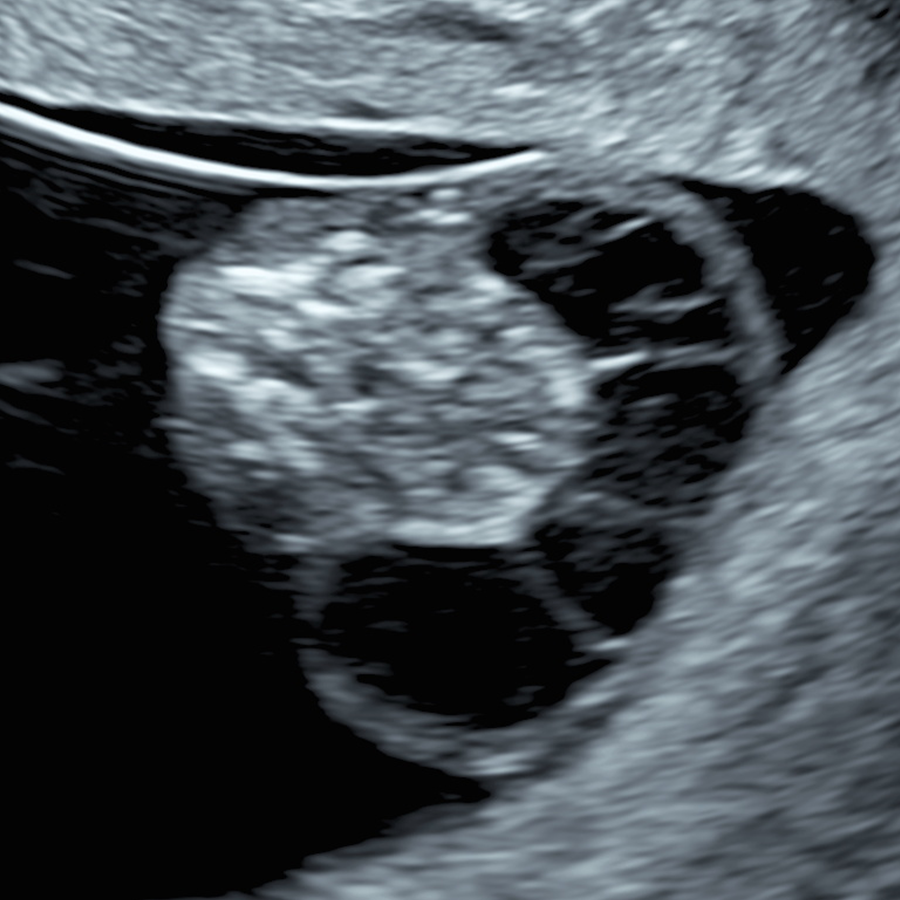

In the “10 Weeks Scan & NIPT” approach, we do not use NT to screen for trisomies 21, 18 and 13, because NIPT does this far better, with a detection rate above 99%. Instead, NT at 10 weeks is used primarily as a powerful early marker of overall fetal health. Cut-offs such as the 95th centile or 2.5 mm (depending on the clinic protocol) are used as a trigger to offer the SMART NT pathway, including extended NIPT and a targeted follow-up scan at 12–13 weeks.

Definition of iNT: iNT denotes increased nuchal translucency at 10 weeks (CRL <45 mm), defined as NT ≥2.5 mm. It is strongly associated with adverse outcomes and should prompt timely, expert evaluation.